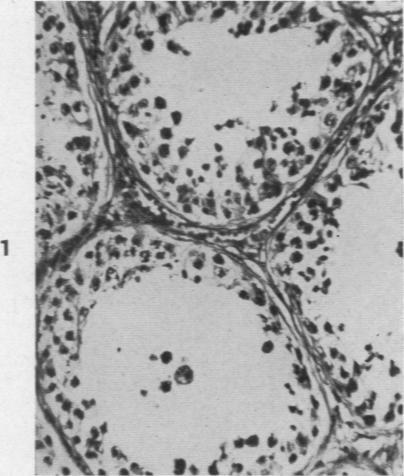

The Histopathology of Acute Mumps Orchitis.

Am J Pathol. 1947 Jul;23(4):637-51.